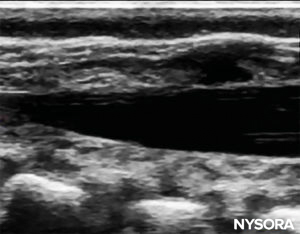

The needle insertion angle is noted during the scan. The needle may be advanced 2–4 mm into the caudal space, and the stylet is removed. To ensure optimal caudal placement of the needle, a small bolus of saline or local anesthetic is administered under US guidance with the probe in the midline (LAX; Figure 10). The probe is positioned as cephalic as needed to visualize the dural sac in the US screen (Figure 11). When the injection starts, you will notice the dura being displaced ventrally, especially in younger children. The spread of local anesthetic can be monitored by moving the probe cephalic up the spine in the midline or in a paramedian sagittal axis (Figure 12). The same dura movement can be visualized with the probe in the SAX in the more cephalic positions (Figures 13 and 14).

FIGURE 11. Dural sac visualized before injection in the longaxis view.

FIGURE 12. Dura movement following injection in the long-axis view.